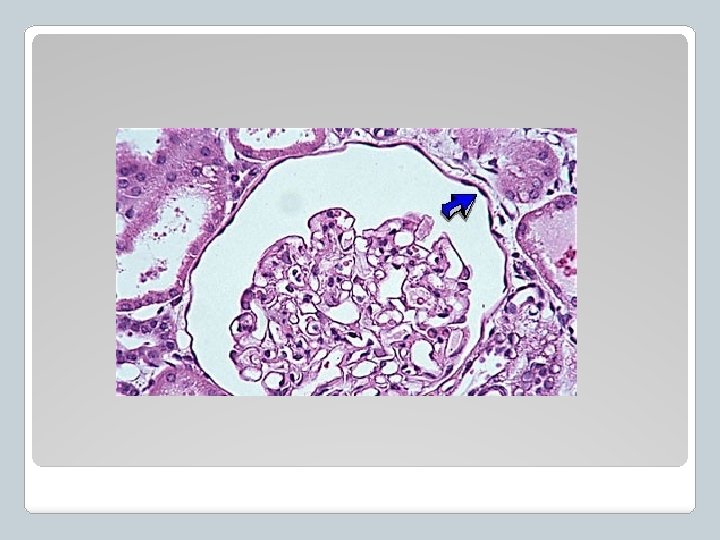

Clasificación del Tejido Epitelial � 1 - Simple ü Una sola capa de células ü Localización: sitios de secreción, excreción o absorción de sustancias. ü Ej. Revestimiento de túbulos renales

�Descripción: una capa de células, las células tienen forma de cilindros cortos, a veces microvellosidades para absorción. �Localizaciones principales: Ø Revestimiento de túbulos renales Ø Conductos glandulares �Funciones: �Secreción y absorción Epitelio cuboideo simple